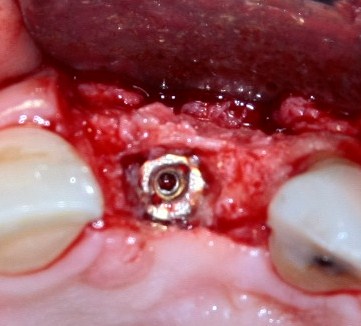

Через три месяца результат:

можно ставить формирователи и заканчивать лечение:

чтобы поставить формирователь: